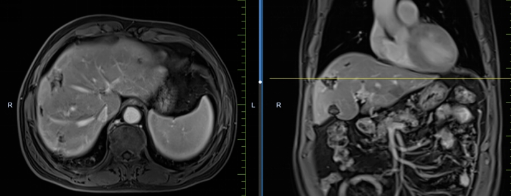

患者馬某某,男,60歲,因腹部不適行胃鏡及腹部CT,提示胃癌、多發(fā)淋巴結(jié)轉(zhuǎn)移、肝轉(zhuǎn)移,胃部病灶大小約11*6cm,淋巴結(jié)最大病灶約6*3cm,肝臟病灶最大約8.8*7cm。經(jīng)6周期化療+免疫,聯(lián)合中醫(yī)中藥后,病灶明顯縮小,進(jìn)入維持治療階段,身體狀況與常人無異。

治療前

治療后